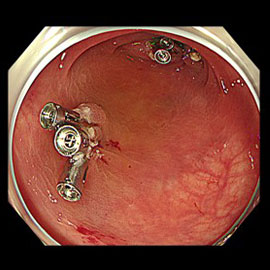

大腸cold polypectomy

1、コールドポリペクトミー

従来は高周波電流を用いて焼灼しつつ切除方法が主流でしたが、この方法は電気を使用しないためより合併症が起こりにくい治療法です。主に小さい病変(10mm未満 腺腫疑)が適応になります。事前に治療のご希望の有無を確認し、検査中治療可能と判断した場合に治療を行います。